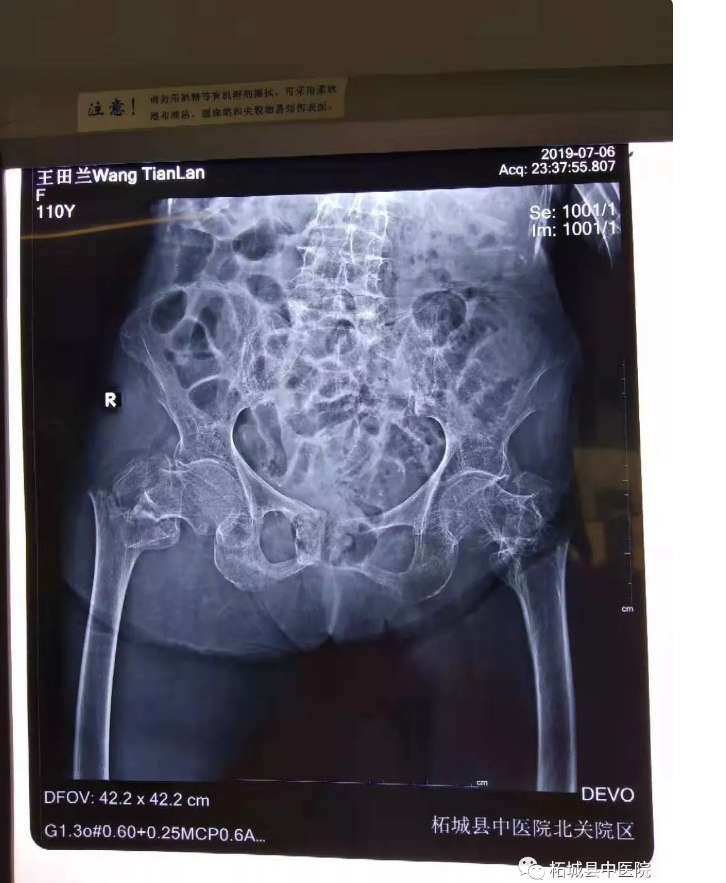

可天有不测风云,一天老人在家活动时不慎滑倒摔到右髋部,当时就感到局部疼痛、肿胀、活动受限,家人急忙把老人送到中医院北关院区找到骨科专家殷晓东寻求诊治,老人年事已高,殷晓东院长接诊后十分重视,第一时间仔细查体后,诊断为右股骨转子间骨折收住骨科。

该老人是一位基础疾病较多的患者,详细检查后,老太太骨折合并有贫血、低蛋白血症、慢性阻塞性肺炎,保守治疗需长期卧床,可能导致坠积性肺炎、褥疮、下肢静脉血栓形成、骨折不愈合等并发症威胁患者生命安全,请北关院区呼吸科王因仲主任、胸痛中心孙全立主任会诊评估,经过多番讨论和家属沟通,参考我院曾经做过多例百岁老人关节置换术后第二天下床走路病例, 终确定人工髋关节置换术的治疗方案。